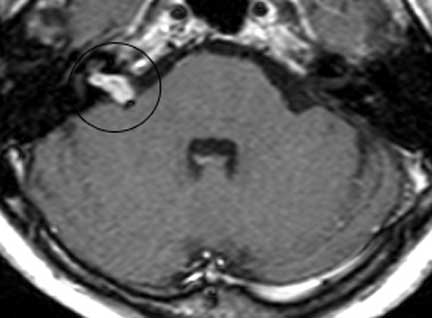

NEURINOMA DEL ACÚSTICO EN PACIENTE DE EDAD AVANZADA CON PÉRDIDA AUDITIVA Y TRASTORNO DEL EQUILIBRIO. EN VISTA DEL ALTO RIESGO PARA CIRUGÍA ABIERTA. SE INDICA RADIOCIRUGÍA

Neurinoma del nervio acústico. El neurinoma está inscrito en un círculo.